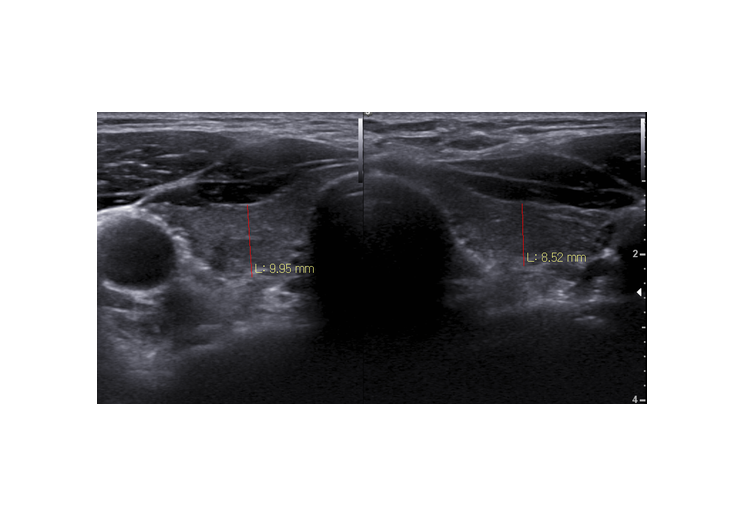

갑상선 초음파; 위축성 갑상선, 갑상선 기능저하